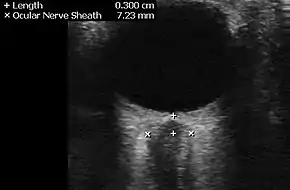

Neuroimaging, usually with computed tomography (CT/CAT) or magnetic resonance imaging (MRI), is used to exclude any mass lesions. In IIH these scans typically appear to be normal, although small or slit-like ventricles, dilatation and buckling[13] of the optic nerve sheaths and "empty sella sign" (flattening of the pituitary gland due to increased pressure) and enlargement of Meckel's caves may be seen.

An MR venogram is also performed in most cases to exclude the possibility of venous sinus stenosis/obstruction or cerebral venous sinus thrombosis.[5][7][8] A contrast-enhanced MRV (ATECO) scan has a high detection rate for abnormal transverse sinus stenoses.[10] These stenoses can be more adequately identified and assessed with catheter cerebral venography and manometry.[11] Buckling of the bilateral optic nerves with increased perineural fluid is also often noted on MRI imaging.